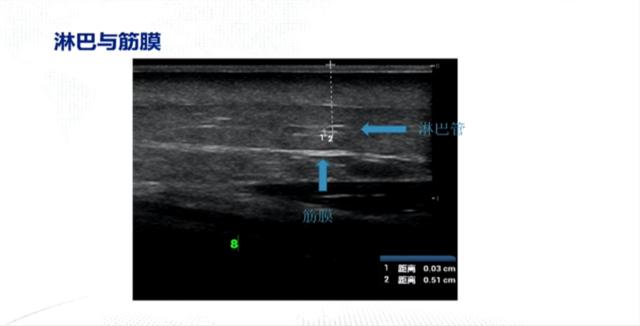

筋膜与淋巴管的比较